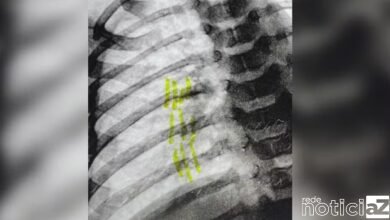

8 de novembro de 20240Mulher sofre lesão após ser empurrada de escada pelo marido